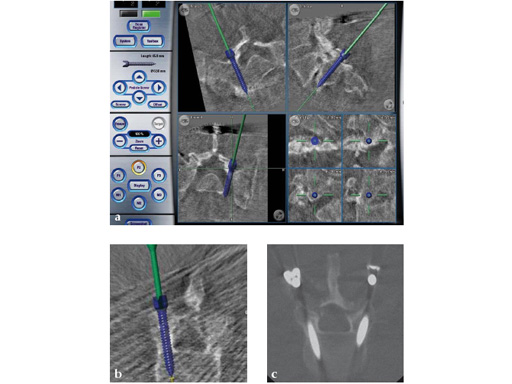

Intraoperative CT scans can be obtained using image-intensification- based isocentric C-arms, portable cone beam CT (O-arm, Medtronic) or true intraoperative CT scanners (iCT). Isocentric C-arms and portable scanners offer the advantage that they can also be used as regular C-arms, however their imaging quality may be inferior to stationary CT scans (Fig 3).

Fig 3ac a Intraoperative CT scans from an image-intensification-based isocentric C-arm. The software allows simulation of various diameter and length screws. bc Comparison of intraoperative simulation and postoperative CT scan shows the high accuracy of CAS.